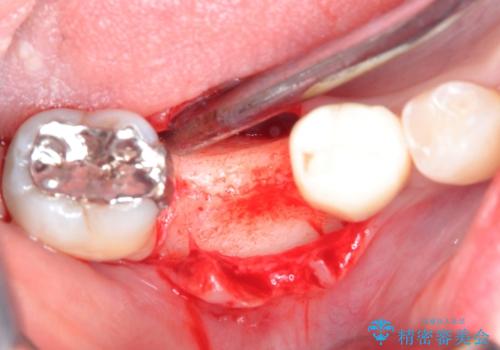

患者様の希望、ブリッジの土台となっている歯の状態、インプラントとブリッジの比較などを総合的に判断して、今回のケースではインプラント治療を選択しました。

- 外科手術のため、術後に痛みや腫れ、違和感を伴います